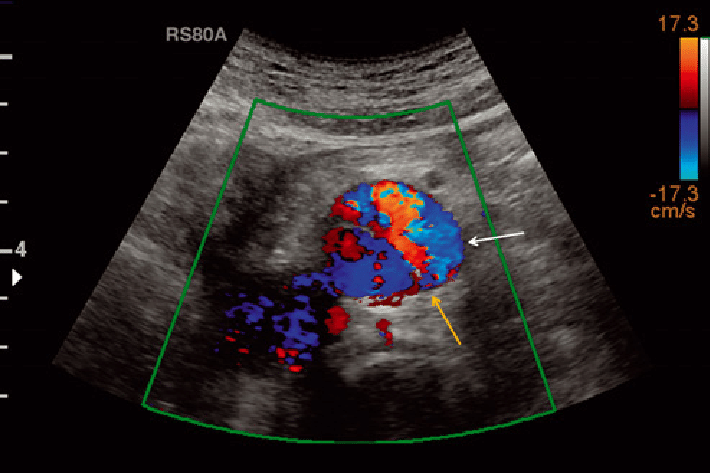

Doppler Ultrasound. (Vascular Ultrasound Imaging)

Ultrasound may also be used to visualise the arteries and veins of the limbs and the neck with the use of Doppler technology. As such, it can reliably detect narrowing of the arteries, varicose veins and blood clots.

Doppler ultrasound (also referred to as vascular diagnostic imaging) is a painless, non invasive means of measuring blood flow. For example Doppler ultrasound can detect problems with abnormal blood flow, where flow may be reduced in veins due to clot (thrombosis), known as Deep Vein Thrombosis (DVT). Ultrasound can also detected narrowing (stenosis) of arteries due to conditions such as atherosclerosis (“hardening of the arteries”); common areas include the neck (carotid arteries) as well as the arteries of both lower limbs.